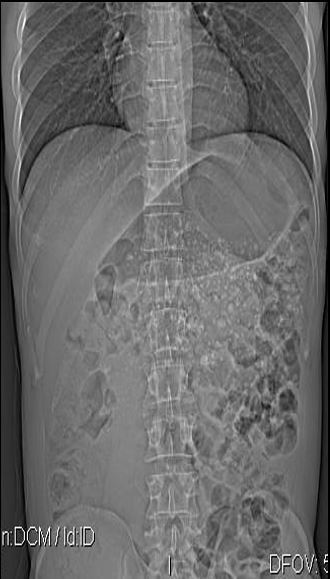

RD SIMPLES DO ABDOME EM DECÚBITO DORSAL.

SETA VERMELHA- ESTÔMAGO

SETA AZUL- CONTORNO DO RIM D

SETA BRANCA – CÓLON TRANSVERSO

SETA VERDE- PSOAS E

SETA NEGRA – FAIXA ADIPOSA LATERAL DO ABDOME ( ESPAÇO PARARRENAL POSTERIOR)

OBSERVE OS PLANOS ADIPOSOS NA CAVIDADE PÉLVICA DELIMITANDO A BEXIGA. ISTO PORQUE TEM TECIDO ADIPOSO CIRCUNDANTE.NUM PACIENTE MAGRO OU EM CRIANÇAS ESTES PLANOS SERIAM INVISÍVEIS.